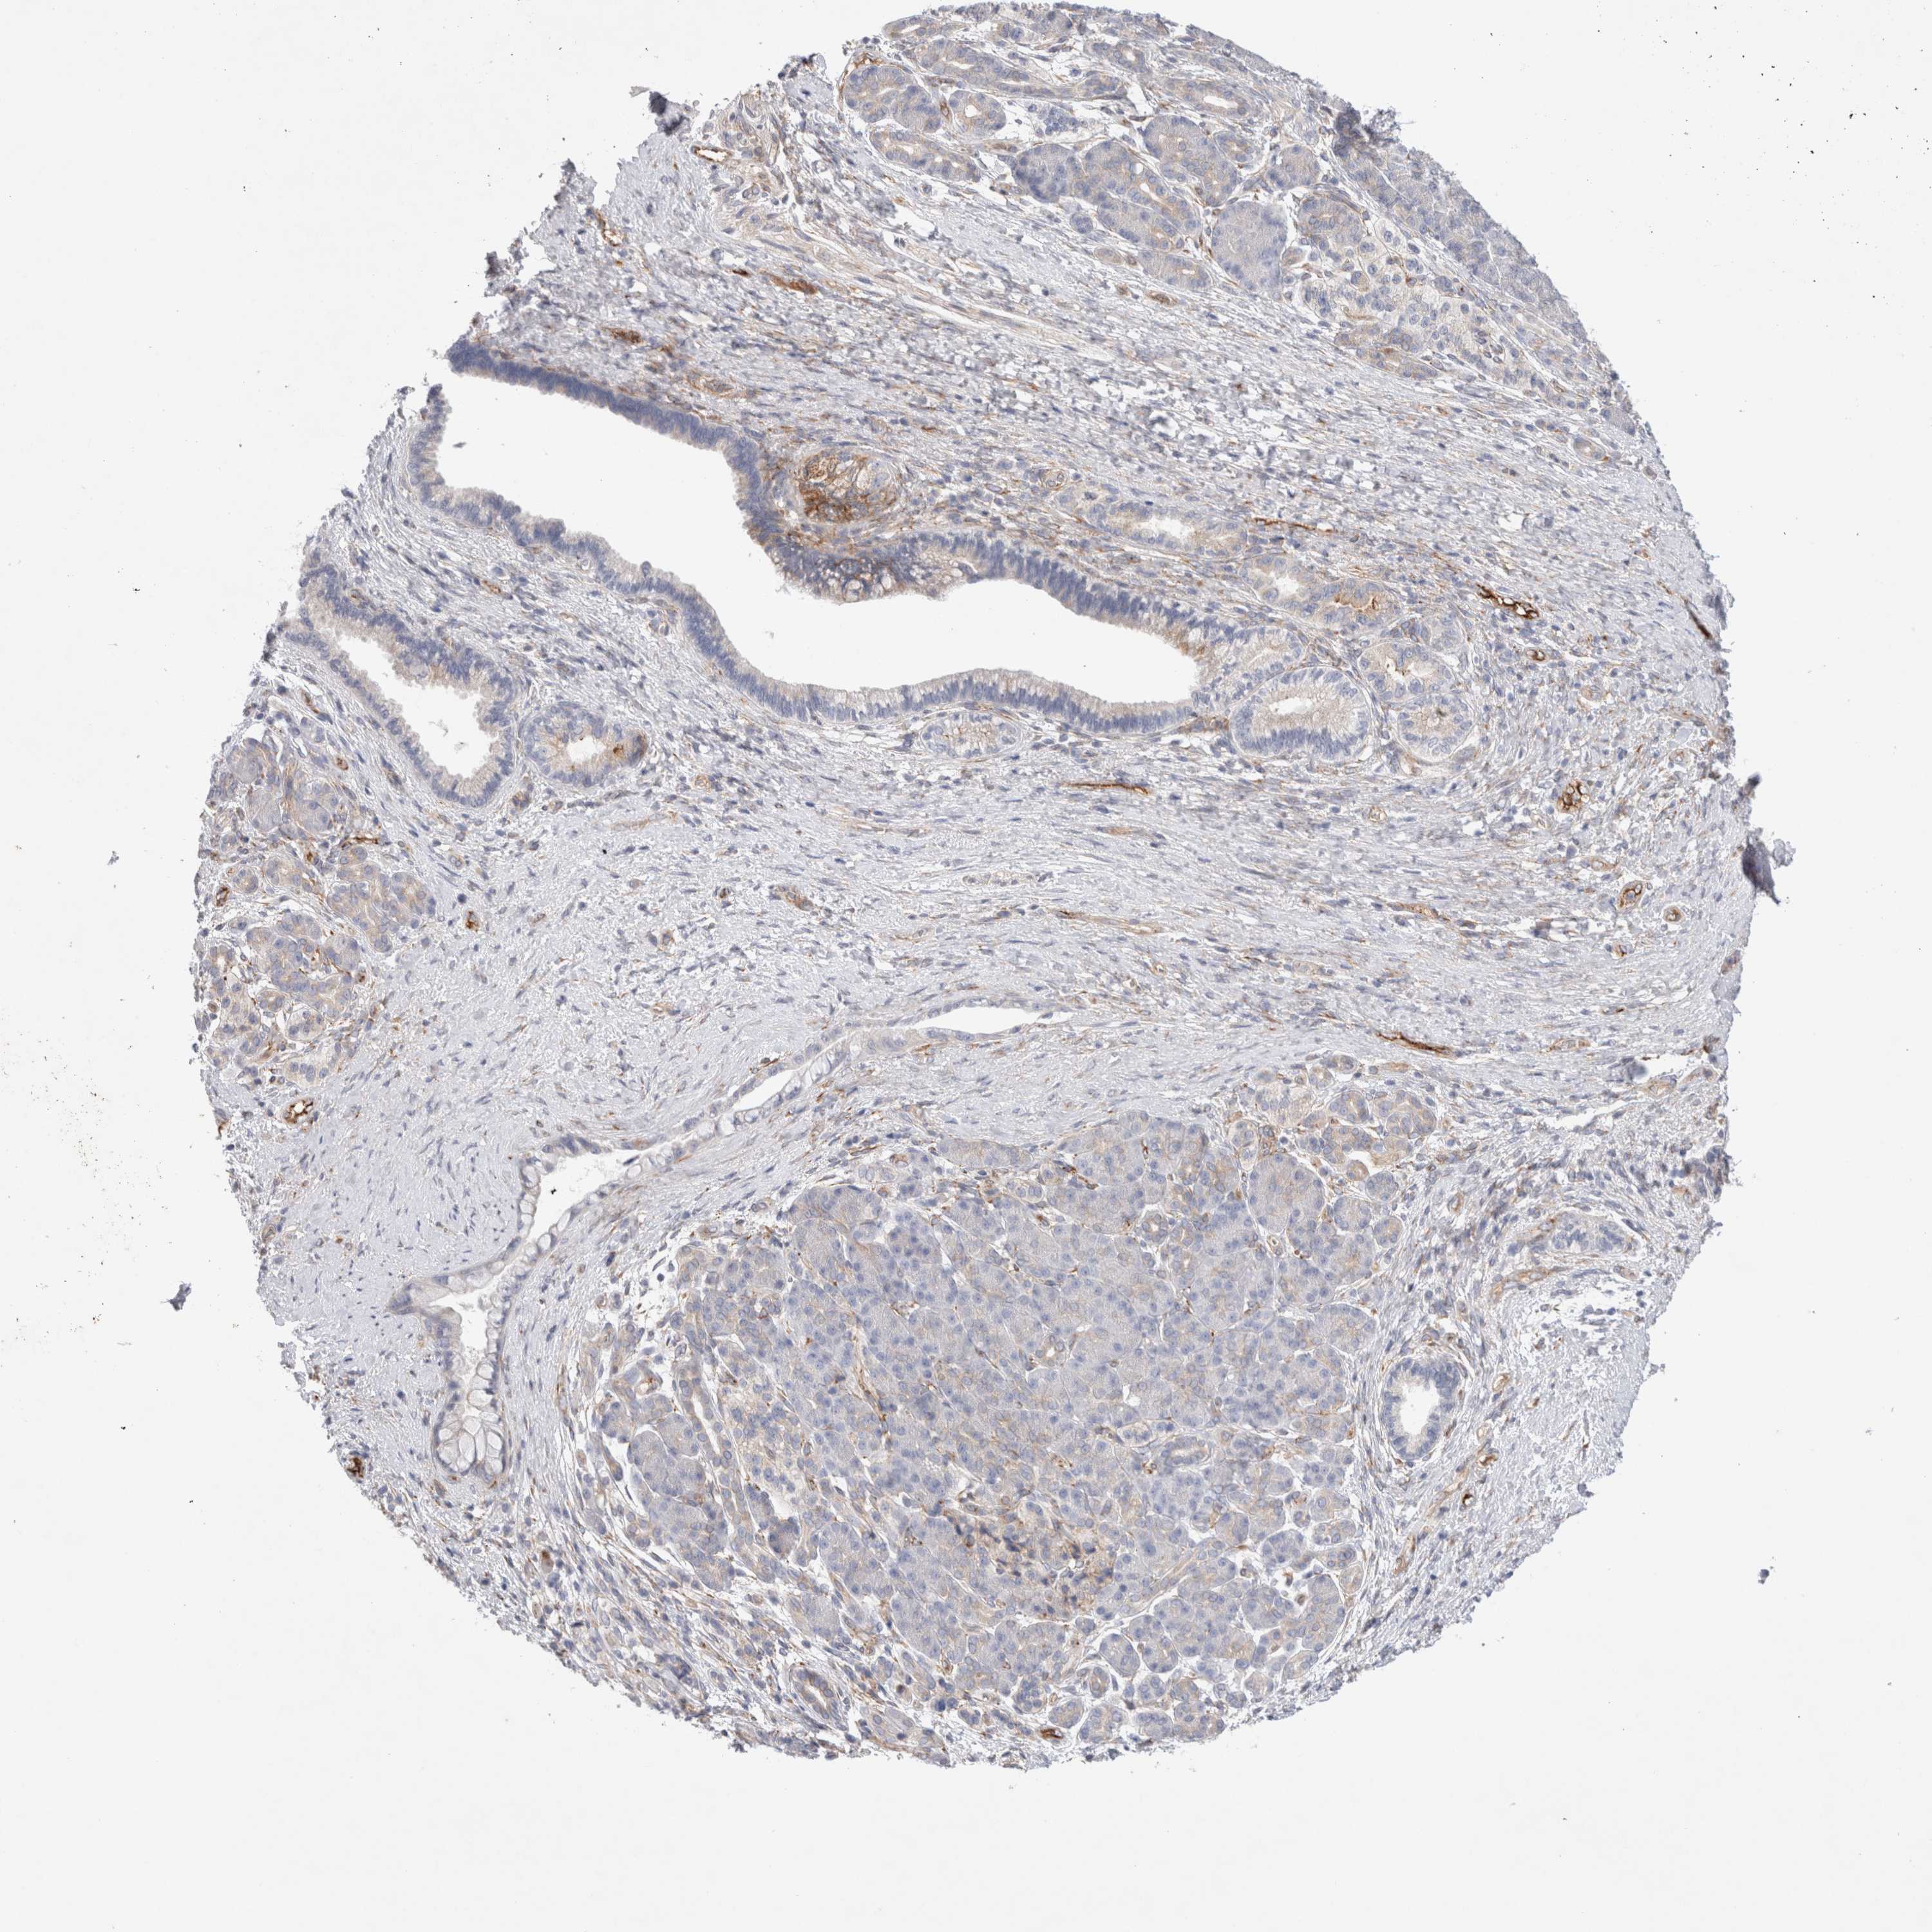

PANCREATIC CANCER - Protein expressioni

A mouse-over function shows sample information and annotation data. Click on an image to view it in a full screen mode. Samples can be filtered based on level of antibody staining by selecting one or several of the following categories: high, medium, low and not detected. The assay and annotation is described here.

Note that samples used for immunohistochemistry by the Human Protein Atlas do not correspond to samples in the TCGA dataset.

Antibody stainingi

Antibody staining in the annotated cell types in the current human tissue is reported as not detected, low, medium, or high, based on conventional immunohistochemistry profiling in selected tissues. This score is based on the combination of the staining intensity and fraction of stained cells.

Each image is clickable and will lead to virtual microscopy that enables deeper exploration of all samples and also displays staining intensity scores, fraction scores and subcellular localization as well as patient and tissue information for each sample.

Antibody HPA014166

Antibody HPA025240

Staining

High

Medium

Low

Not detected

Intensity

Strong

Moderate

Weak

Negative

Quantity

>75%

75%-25%

<25%

None

Location

Nuclear

Cytoplasmic/membranous

Cytoplasmic/membranous,nuclear

Adenocarcinoma, NOS

Adenocarcinoma, metastatic, NOS